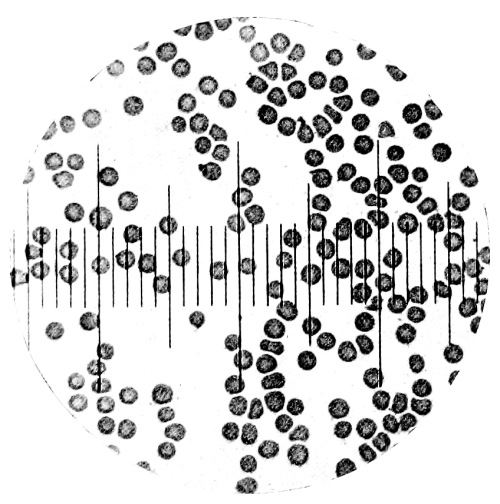

8. Measurement of Blood Corpuscles (human) 97

9. Measurement of Blood Corpuscles (sheep) 97